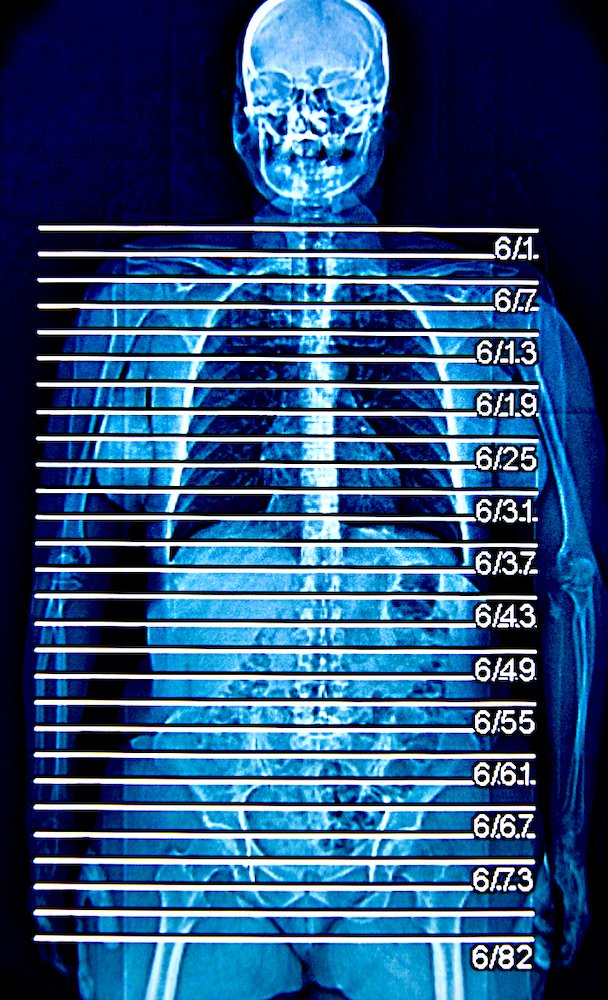

saturday night fever (boy meets girl diptych)

Selected for July/Aug 2022 exhibition in Art No.23’s Barcelona gallery.